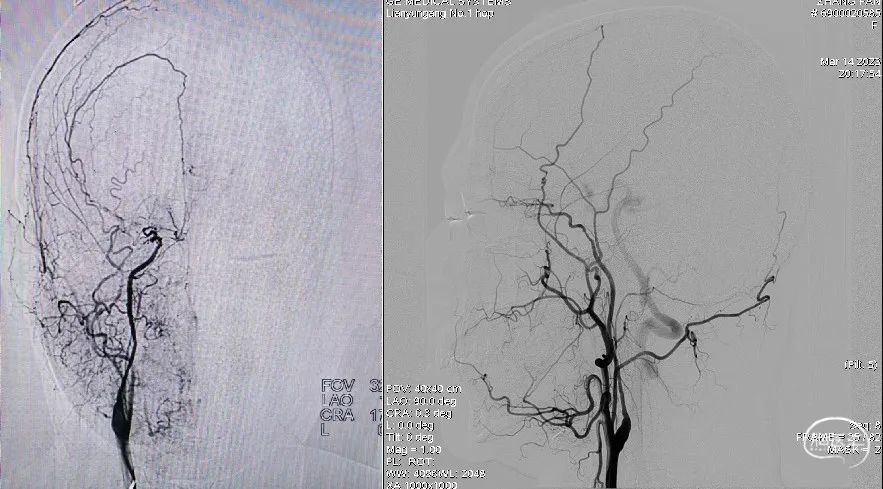

术后多角度造影及蒙片提示两枚支架桥接良好,支架张开贴壁,载瘤动脉通畅,动脉瘤内造影剂进一步瘀滞。

术后蒙片提示支架桥接良好,张开贴壁,动脉瘤内造影剂瘀滞。

术后多角度造影及蒙片提示支架打开贴壁良好,载瘤动脉通畅。

术后蒙片提示支架张开贴壁良好